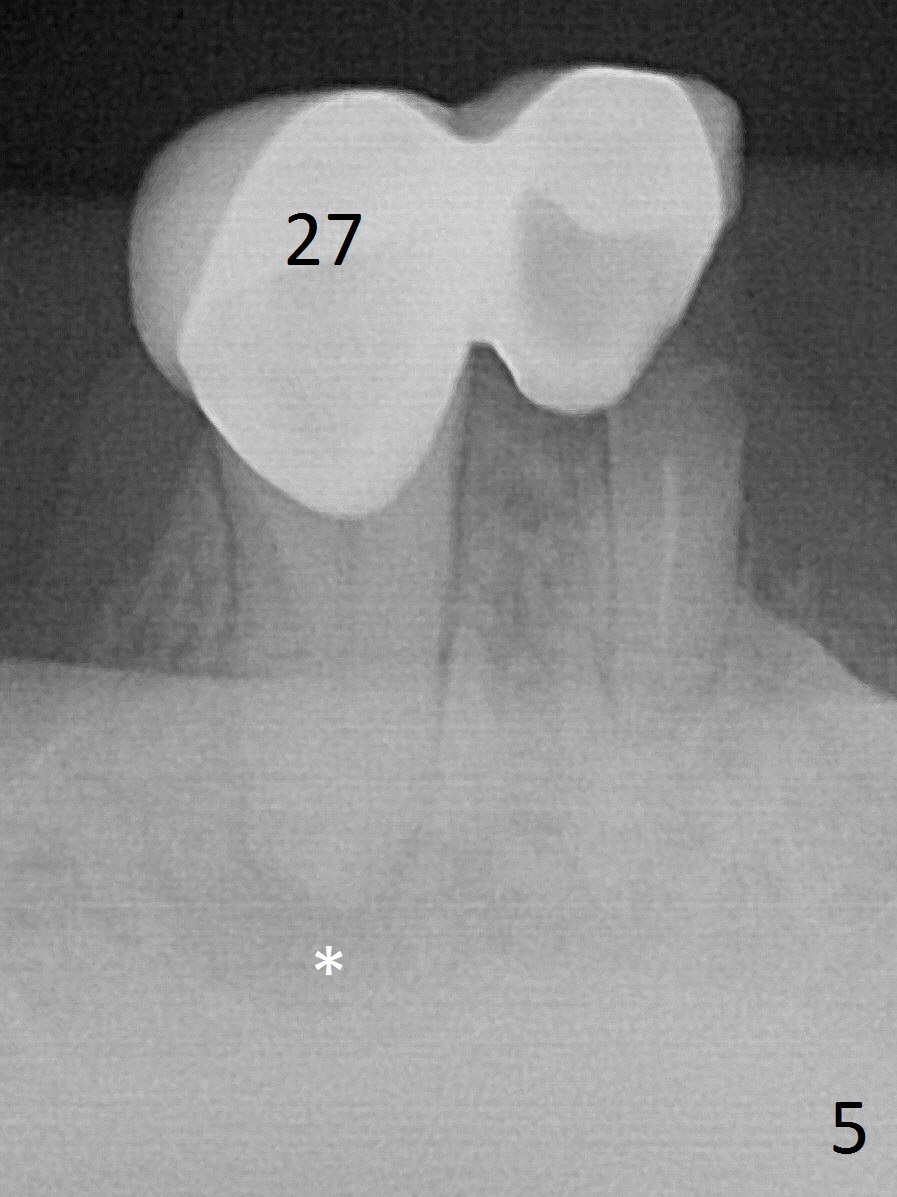

A 62-year-old woman has poor dentition (Fig.1). The most critical area is the upper left anterior: #9-11, which were extracted 4 months earlier (Fig.2). Implants will be placed at #9 and 11 with fabrication of a provisional bridge (Fig.3). After incision, use Magic Split to start bone expansion, followed by micro-osteotomes 1 and 1.5 mm and Magic Osteotomes 3 and 3.8 mm. If the transition between 1.5 and 3 mm osteotomes is not smooth, apply RT2. Place the smallest bone-level implants (for hybrid denture in the future) with gold coated abutments. There should be no interference with or without the partials and in and out. Next step should be removing splinted crowns at #26 and 27 (Fig.1), RCT for #27 and immediate implant at #26 (Fig.5,6 Metronidazole). In fact the splinted crowns at #26 and 27 were lost last week. The patient thinks that she needs 2 implants. The next one is to remove the crown at #5 for RCT (Fig.4).